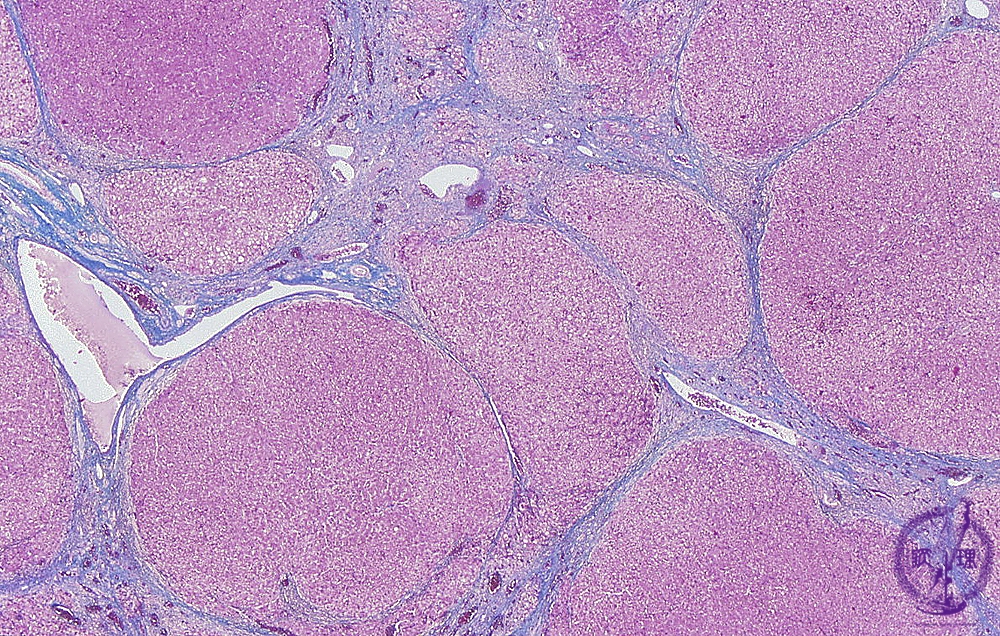

- 10.Liver

- ★(1)Viral hepatitis, cirrhosis

Microscopic image (AZAN trichrome stain, low power): Liver cirrhosis due to chronic hepatitis. There is a loss of lobular architecture with effacement of normal parenchyma by regenerative hepatocellular nodules of various sizes. Narrow fibrous septa surround and separate regenerative nodule.

Click the image to see the enlarged image.